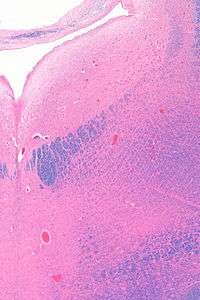

![]() Micrograph showing the locus coeruleus. HE-LFB stain. | |